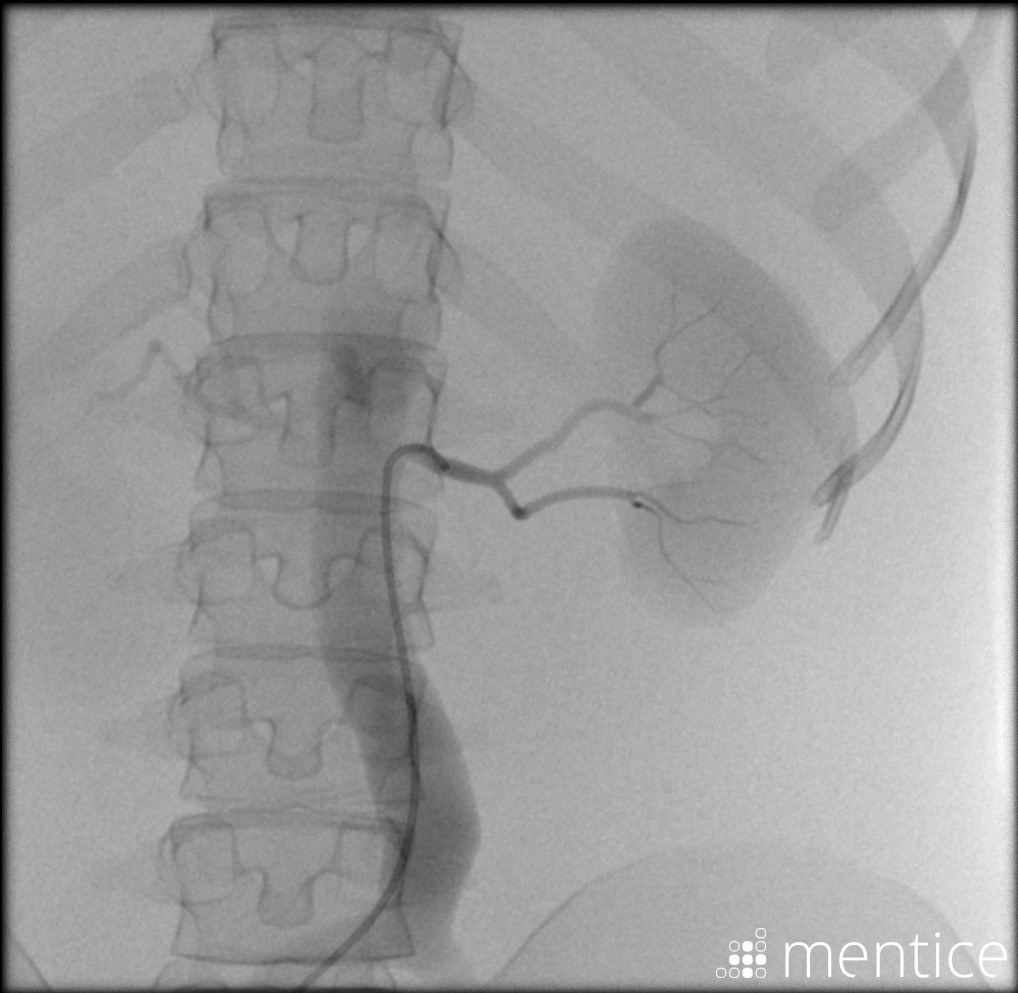

Simuladores Endovanculares.

módulos内血管分发

Aquíhayuna listademódulosundonibles concatibles con el simulador vist g5(Versiónforporidenteyy lab,没有兼容的孔血管y vist灯)。Esta listaestántancoreeevolución,没有Dude en advertarla promicy ... los dutallesestándisponibles haciendo clic en eltítulodelmódulo(网站蒙黛尔,enInglés)